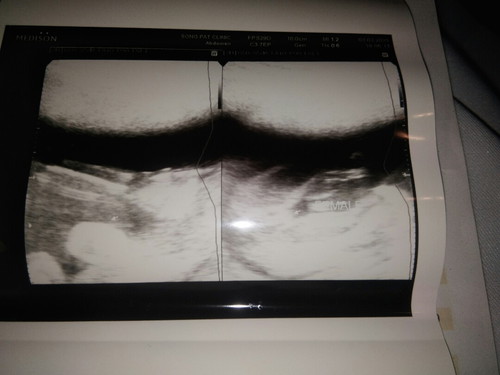

ซาวตอน 22w หญิงหรือชายช่วยบอกที

คืออยากรู้เพศน้องมากเลยค่ะ โอกาศพลาดมีไหมค่ะ

มีข้อความเขียนไว้นะคะ น้องน่าจะเป็น ผญ ค่ั

มันเขียนไว้อยู่นะคะผู้หญิว

คุณหมอเขียนไว้ ผญ. นะคะ

หมอพิมว่า ผู้หญิงค่ะ

Female = ผู้หญิงค่ะ

ผู้หญิงค่ะ